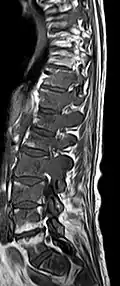

- Vergleich CT / MRT bei osteolytischen Metastasen eines Mammakarzinoms in der Wirbelsäule

Sagittale native T1-gewichtete MRT -

Sagittale native T1-gewichtete MRT. Deutlich sichtbar die Ausdehnung bis in die Bogenwurzeln.